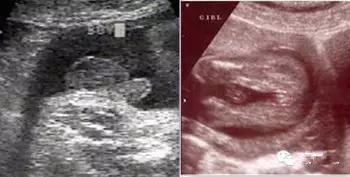

如果是男孩,B超影像可以看到*丸睾**的显影,即小茶壶样,或有点像菌状的东西;女孩子则可以看到小阴唇的显影,呈三条线状。最大的要点就是“三条线”和“凸出的东西”。

但是对于没有学过影像学的非专业人士很难看懂,更不要说看出这样的形状,不建议孕妇盲目判断。